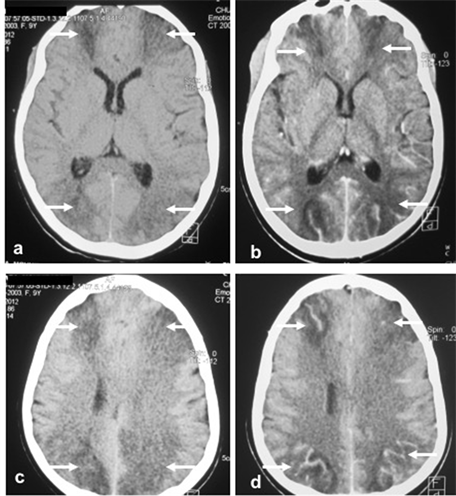

An encephalic computed tomography (CT) scan (Figure 1) performed with and without injection of iodinated contrast medium showed hypodensity ranges of approximately 20 Hounsfield units related to junctional seat cytotoxic edema with vascular repealing after injection, and without mass detected. There was no abnormality of the pituitary region. A peri-critical electroencephalogram (EEG) could not be performed.

Figure 1. Encephalic CT scan showed hypodensity ranges of approximately 20 Hounsfield units related to junctional seat cytotoxic edema (arrows) with vascular repealing after injection, without mass detected and no abnormality of the pituitary region.

In our case, the child presented neurological disorders: recurrent convulsions, coma, aphasia, troubles of walking. These events evoked in one hand, brain edema associated with fluid retention related to the hyperaldosteronism; on the other hand, a secondary cerebral localization of the CS although the brain metastases are very rare in this disease [8] [9] . CSF was sterile and chemically normal. Brain CT performed without and with injection of iodinated contrast material showed hypodensity ranges of about 20 Hounsfield units related to a junctional seat cytotoxic edema (Figure 1) with vascular repealing after injection, and without mass detected. A cerebral MRI, and a possible neurosurgical intervention, with histology of a biopsy specimen would have been of great contribution to the diagnosis.